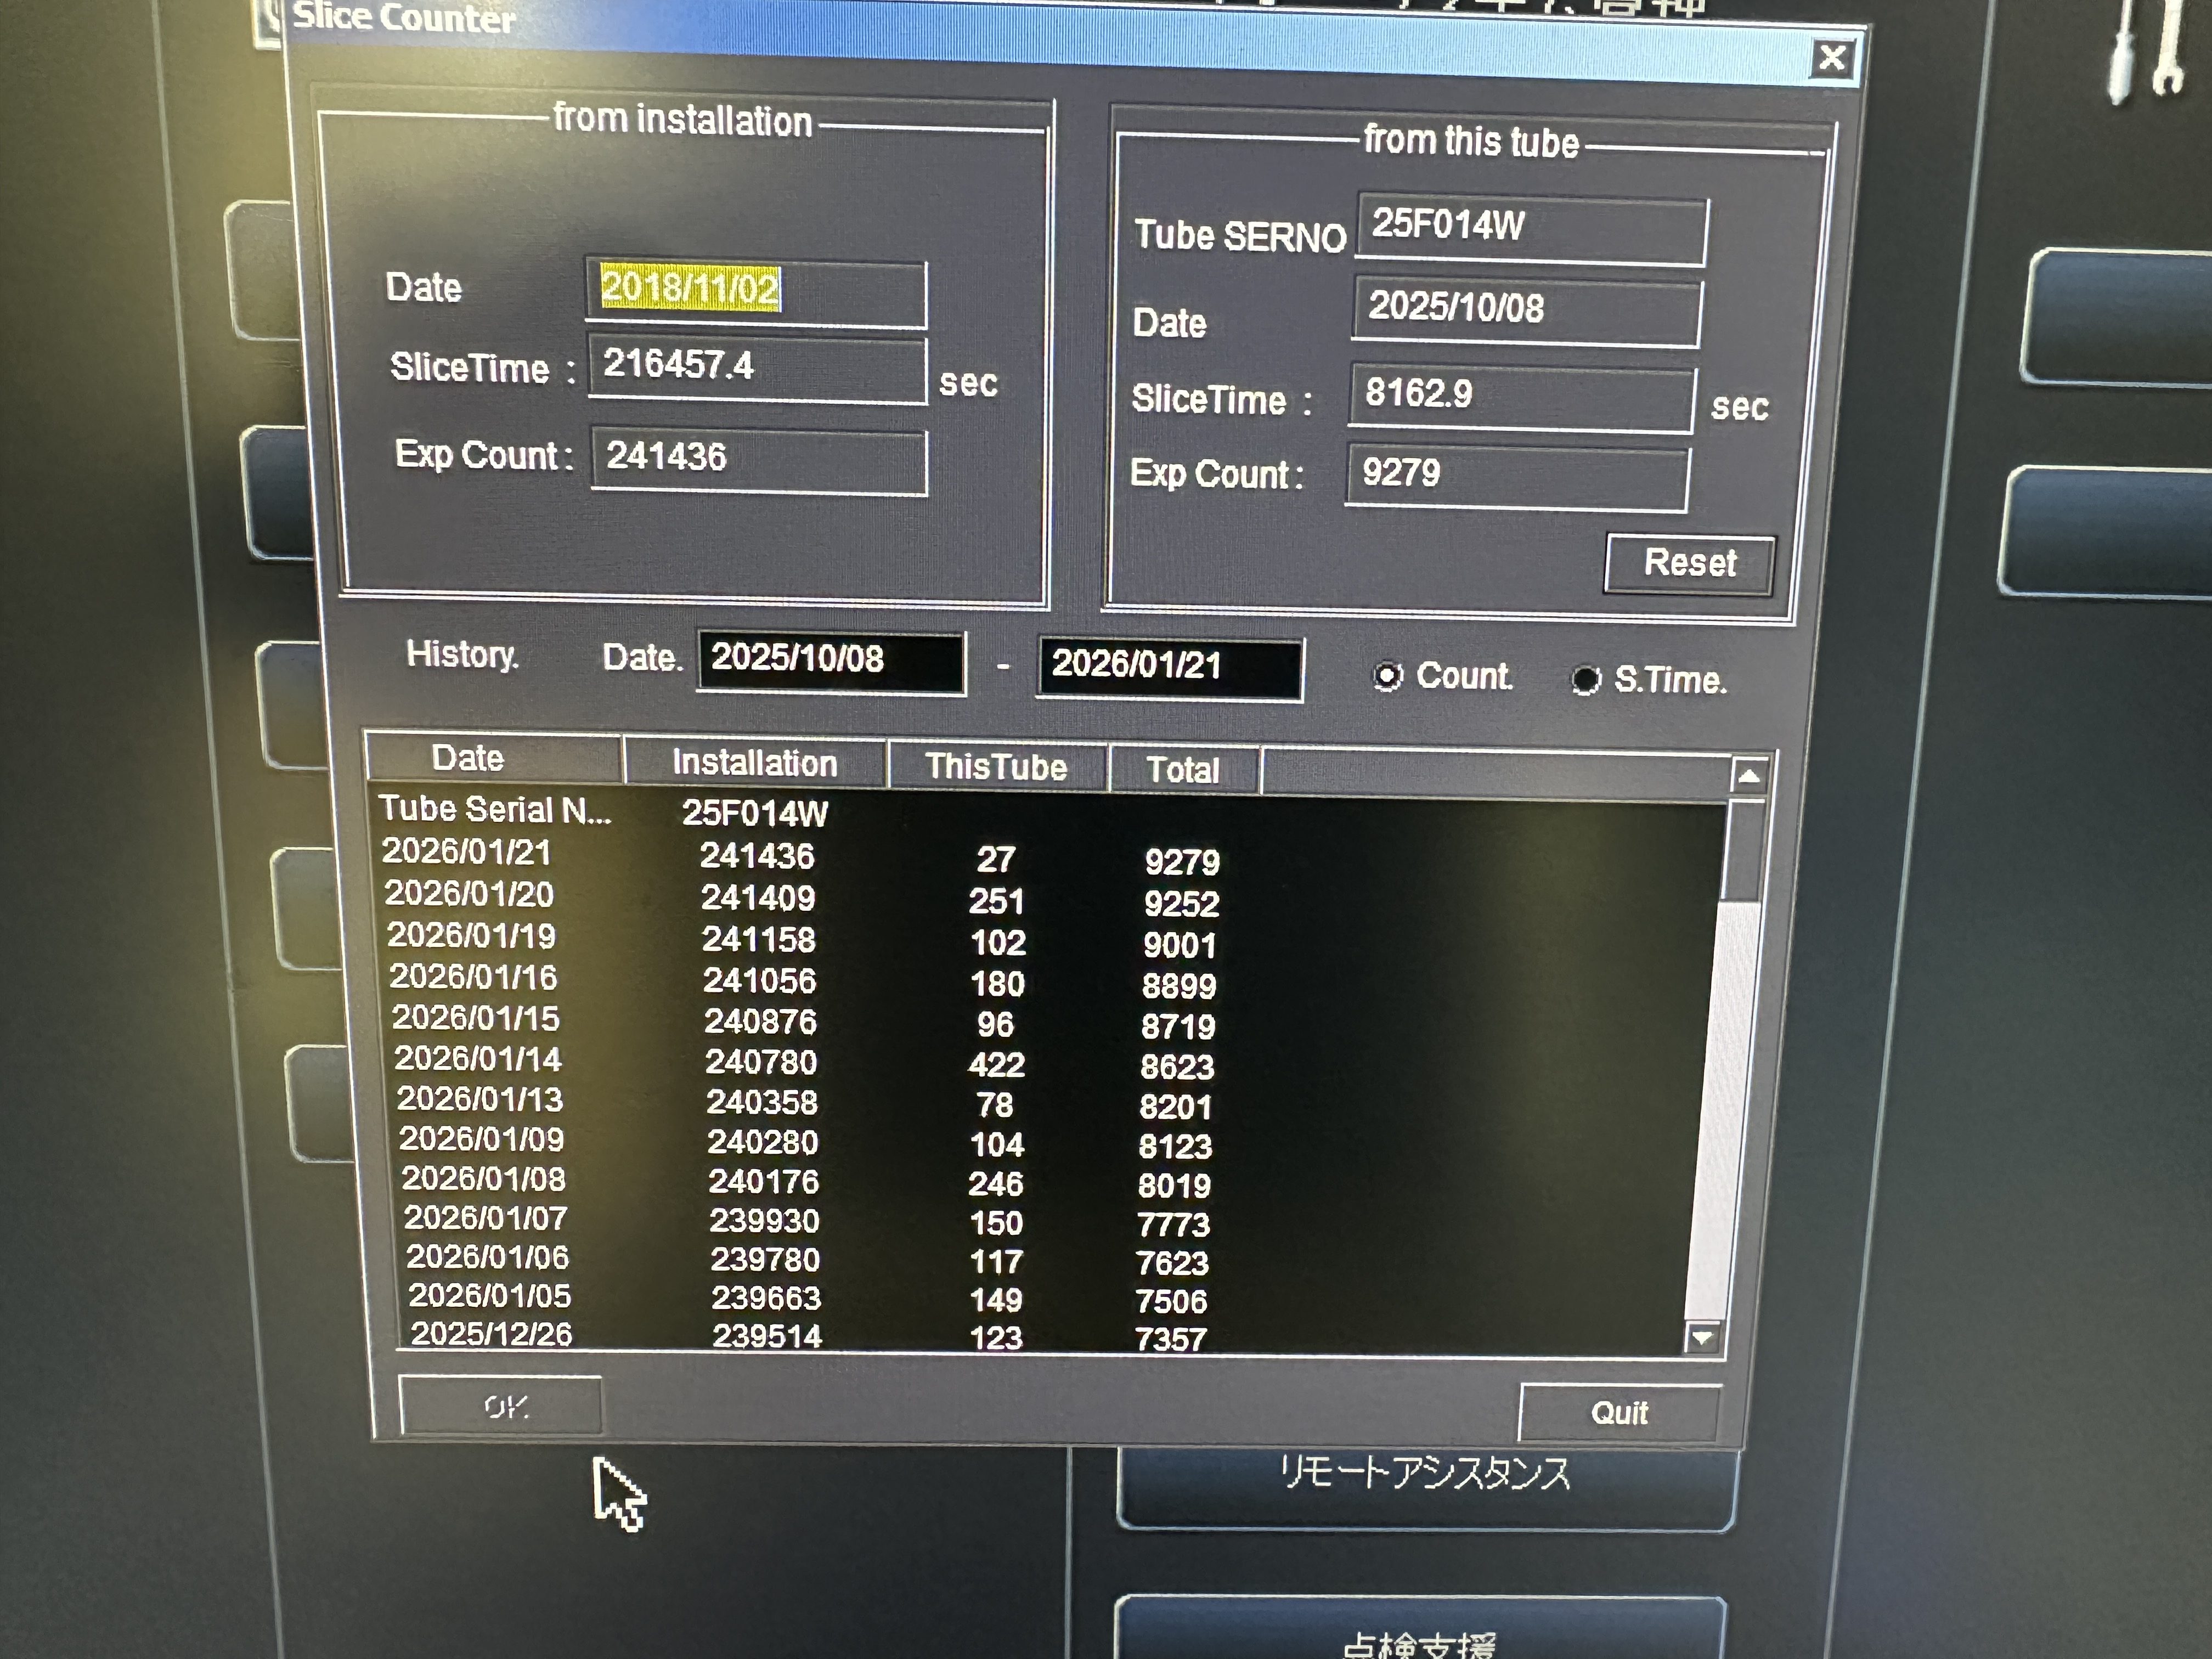

| Tube Manufactured | : | June 2025 (Almost new tube) |

| Tube Replaced | : | October 2025 |

| Tube Slice Time | : | 9779 sec |

| Tube Exposure Count | : | 11,157 |